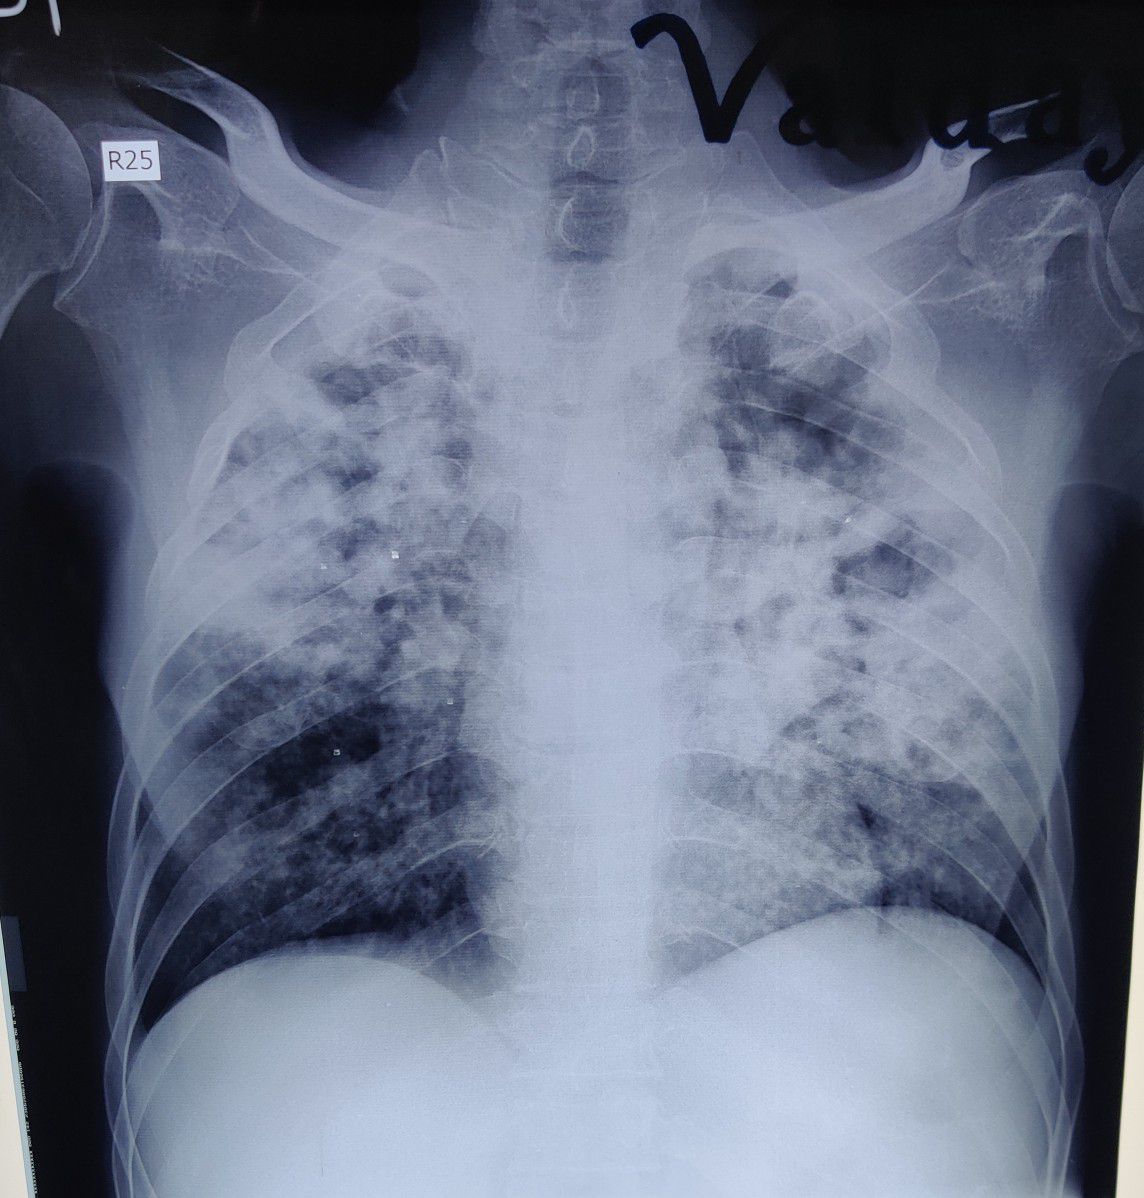

What is the diagnosis?

Covid

Cap